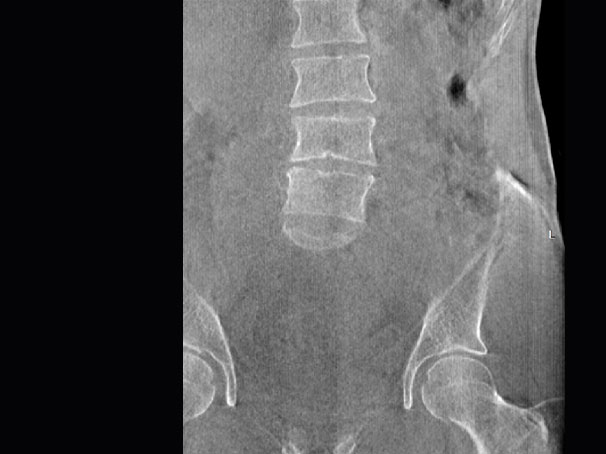

腰椎

髋关节